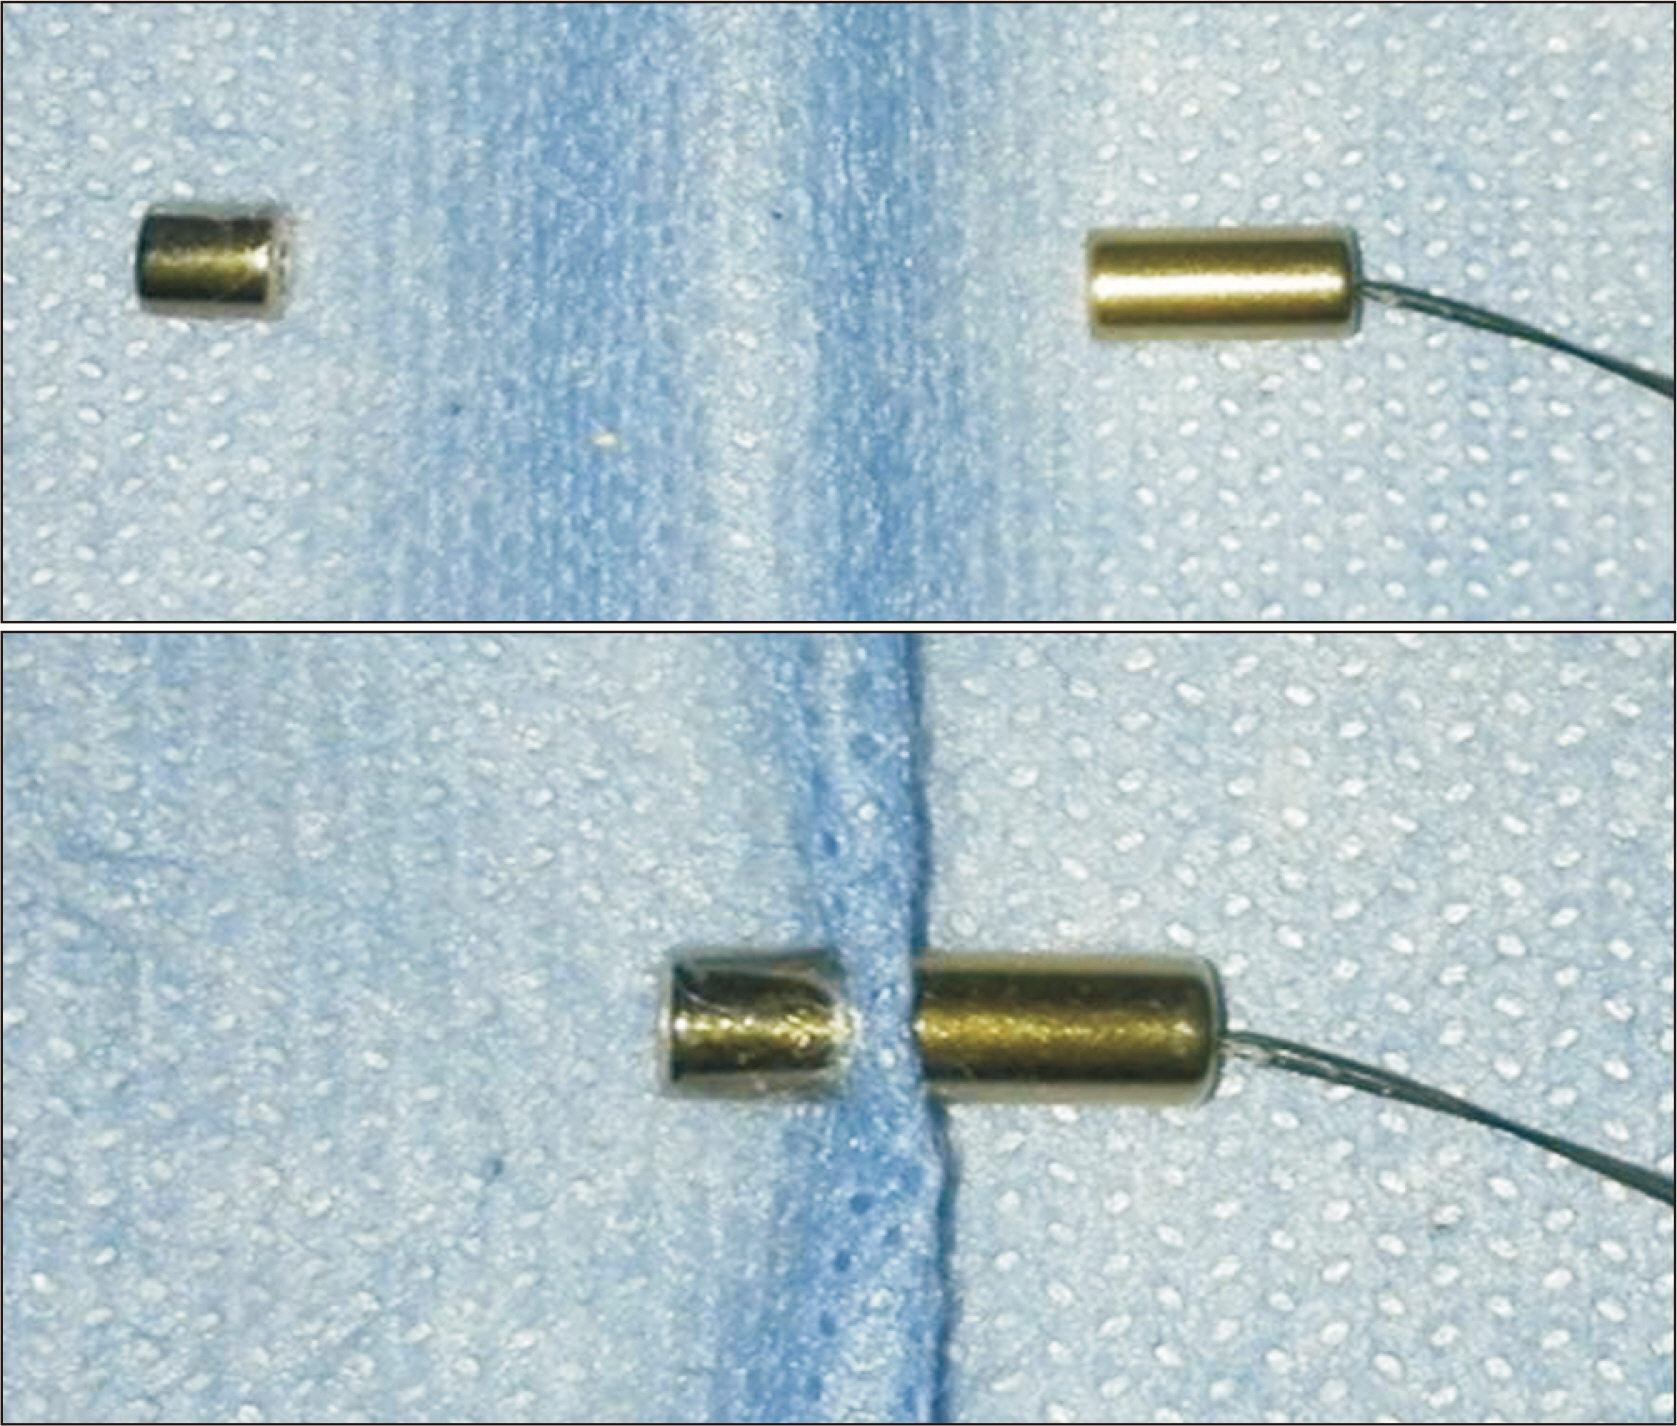

- Bile duct injuries are a serious issue, and their surgical treatment carries the risk of morbidity and mortality. In selected cases, non-surgical treatments are possible, even for total strictures. We outline the technique and results of using magnetic compression anastomosis (MCA) to treat post-cholecystectomy bile duct stricture (PCBDS), in two female patients. Initially, a bilio-cutaneous tract was established via external biliary drainage, followed by the positioning of both endoscopic and percutaneous biliary magnets. After their approximation and subsequent removal, a fully covered self-expandable metal stent (FCSEMS) was deployed across the stricture. The magnet coupling was successfully achieved within the first two weeks of placement. The FCSEMS was maintained for durations of 12 and 16 months. Follow-up durations were 28 and 15 months post-FCSEMS removal. Both patients remain asymptomatic, with normal laboratory and imaging studies, and no adverse events were reported. MCA proves to be a safe and effective method for treating selected cases of total PCBDS. However, further studies and long-term follow-up are required to fully assess the efficacy of this technique.

Article5. Jang SI, Cho JH, Lee DK. 2020; Magnetic compression anastomosis for the treatment of post-transplant biliary stricture. Clin Endosc. 53:266–275. DOI: 10.5946/ce.2020.095. PMID: 32506893. PMCID: PMC7280848.

Article6. Li Y, Sun H, Yan X, Wang S, Dong D, Liu X, et al. 2020; Magnetic compression anastomosis for the treatment of benign biliary strictures: a clinical study from China. Surg Endosc. 34:2541–2550. DOI: 10.1007/s00464-019-07063-8. PMID: 31399950.

Article7. Jang SI, Choi J, Lee DK. 2015; Magnetic compression anastomosis for treatment of benign biliary stricture. Dig Endosc. 27:239–249. DOI: 10.1111/den.12319. PMID: 24905938.

Article11. Yamanouchi E, Kumano R, Kobayashi K, Hattori T, Matsumoto J, Oonishi T, et al. 2002; [Treatment for bowel or biliary obstruction by magnetic compression anastomosis development of Yamanouchi's method and its clinical evaluation]. J Nippon Med Sch. 69:471–475. Japanese. DOI: 10.1272/jnms.69.471. PMID: 12382010.

Article13. Itoi T, Yamanouchi E, Ikeuchi N, Kasuya K, Iwamoto H, Tsuchida A. 2010; Magnetic compression duct-to-duct anastomosis for biliary obstruction in a patient with living donor liver transplantation. Gut Liver. 4 Suppl 1(Suppl 1):S96–S98. DOI: 10.5009/gnl.2010.4.S1.S96. PMID: 21103303. PMCID: PMC2989546.

Article14. Jang SI, Kim JH, Won JY, Lee KH, Kim HW, You JW, et al. 2011; Magnetic compression anastomosis is useful in biliary anastomotic strictures after living donor liver transplantation. Gastrointest Endosc. 74:1040–1048. DOI: 10.1016/j.gie.2011.06.026. PMID: 21855872.

Article15. Jang SI, Rhee K, Kim H, Kim YH, Yun J, Lee KH, et al. 2014; Recanalization of refractory benign biliary stricture using magnetic compression anastomosis. Endoscopy. 46:70–74. DOI: 10.1055/s-0033-1358907. PMID: 24254385.

Article16. Jang SI, Do MY, Lee SY, Cho JH, Joo SM, Lee KH, et al. 2024; Magnetic compression anastomosis for the treatment of complete biliary obstruction after cholecystectomy. Gastrointest Endosc. 100:1053–1060.e1054. DOI: 10.1016/j.gie.2024.05.009. PMID: 38762041.

Article17. Do MY, Jang SI, Cho JH, Joo SM, Lee DK. 2022; Magnetic compression anastomosis for treatment of biliary stricture after cholecystectomy. VideoGIE. 7:253–255. DOI: 10.1016/j.vgie.2022.03.005. PMID: 35815159. PMCID: PMC9264143.

Article18. Ödemiş B, Başpınar B, Tola M, Torun S. 2022; Magnetic compression anastomosis is a good treatment option for patients with completely obstructed benign biliary strictures: a case series study. Dig Dis Sci. 67:4906–4918. DOI: 10.1007/s10620-022-07381-3. PMID: 35050430.